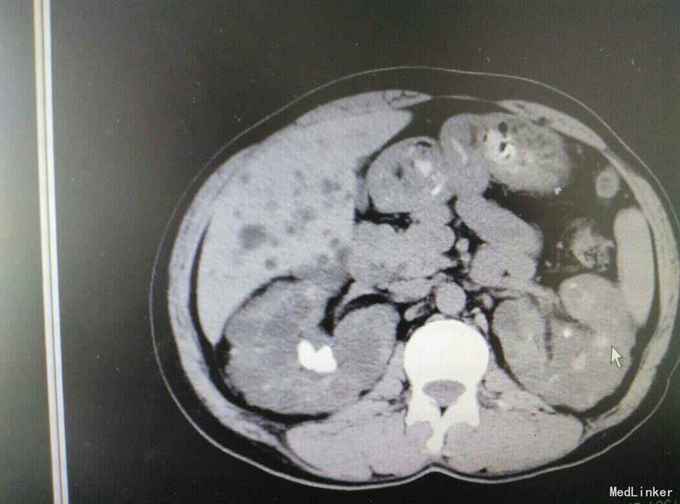

多囊肾合并双肾结石并积水

肾结石 多囊肾 多囊肝

患者47岁,男,因‘’腰痛伴、血尿伴发热7天‘入院。 患者既往有‘高血压’病史多年,7天前无明显诱因出现腰痛,随后出现肉眼血尿,为程肉眼血尿,当天晚上出现发热,最高体温38.6摄氏度,予以对症处理后,发热可退去,但症状反复,患者为求进一步进一步治疗遂来我院。

多囊肾,双肾结石,多囊肝,高血压